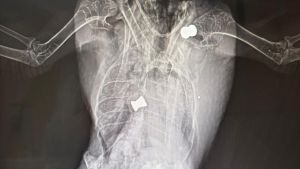

Schock in Meßkirch: Taube mit zwei Projektilen gefunden

Auf einen mutmaßlichen Fall von Tierquälerei in einem Wohngebiet in Meßkirch hat ein Leser den SÜDKURIER aufmerksam gemacht. Was er Ende März in...